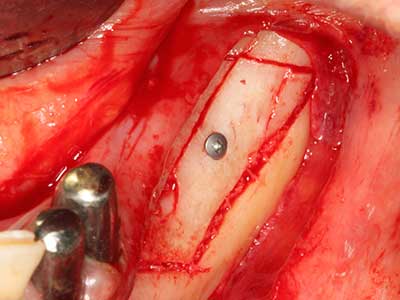

Indication: Bone splitting

Bone tissue is not simply a mineral structure but also contains a substantial proportion of collagen fibres. This means it not only has good compressive strength but also a degree of flexibility, which can be taken advantage of when performing bone augmentations. In the classical expansion procedure using bone splitting, the atrophied alveolar ridge is split longitudinally and carefully expanded after reaching an adequate osteotomy depth (Fig. 13-16), ideally without substantial removal of the periosteum (Brugnami, Caiazzo et al. 2014, Stricker, Fleiner et al. 2014). Screw and plate systems with increasing expansion distance have proven effective in separating the two bone lamellae while remaining below the fracture threshold. In general, residual bone widths of at least 3–4 mm are required (Chiapasco, Zaniboni et al. 2006) to guarantee adequate flexibility and sufficient bone coverage of the future implants. If necessary, a vertical relief osteotomy on one or both sides can improve flexibility. A combination with additional augmentation techniques, particularly on the buccal side, has been described as an alternative to the classical technique.

The splitting procedure is particularly atraumatic and there is no significant loss of dimension when using piezosaws, and there are no significant differences between implants in split jaws and implants in an alveolar ridge without a bone deficit (Chiapasco, Zaniboni et al. 2006, Danza, Guidi et al. 2009). However, sufficient continuous irrigation is essential, particularly with locally restricted and deep splitting to prevent thermal stress in the apical osteotomy regions.